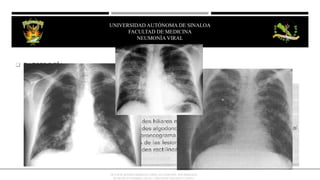

 RADIOGRAFÍA De gran valor para precisar el dx

 RADIOLOGÍA:

IMAGEN

• Lesiones localizadas en la base,

solo afectan un segmento o lóbulo

y describe derrame pleural.

• Crecimiento hiliar

• Imagen nodular pseudotumoral

(benigna)